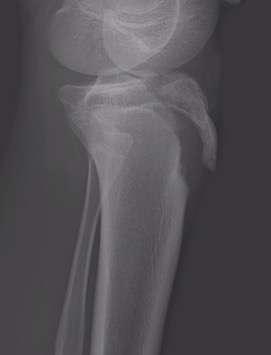

CT / MRI scan

CT scan - ensure fracture doesn't involve the physis / disrupt articular surface

Type IB

Type IIB

Type III

Comminuted Type III